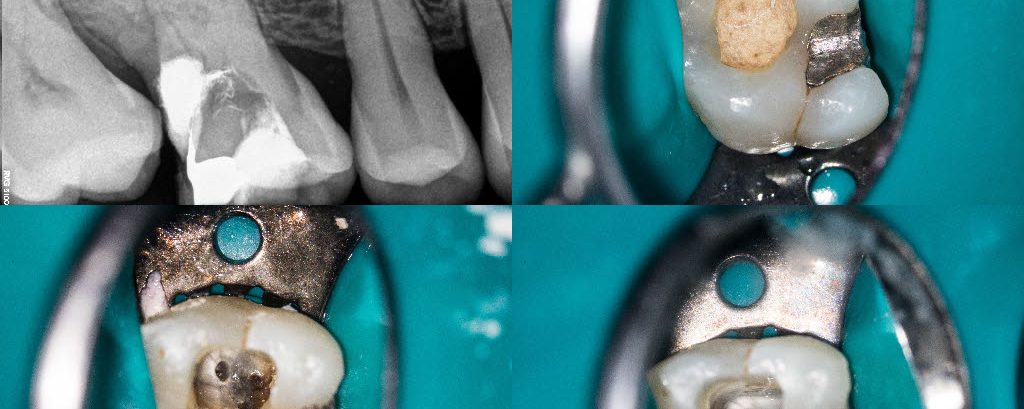

Cracked lower second molar

Yesterdays complete. Findings were a DMR crack with no associated isolated probings and recurrent caries under the old M resin. Stone removal. 3 mesial canals and resin core. Advised a crown.